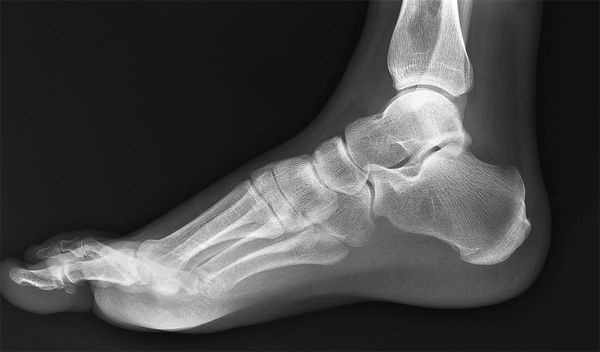

Диагностика патологических процессов методом рентгенографии заключается в получении и анализе двухмерного изображения тканей на снимке (рентгенограмме), получаемого при воздействии на орган рентгеновскими лучами. Наиболее отчетливо на снимке визуализированы объекты, имеющее более плотную структуру. Рентген голеностопного сустава позволяет с высокой степенью точности оценить состояние костных тканей, из которых он состоит. К ним относятся:

- Большеберцовая кость голени. В нижнем эпифизе она переходит в медиальную лодыжку, суставная поверхность которой охватывает таранную кость.

- Малоберцовая, сочлененная внизу с таранной костью. Дистальный конец кости является наружной лодыжкой блока голеностопного сустава.

- Таранная кость (надпяточная), являющаяся нижней частью голеностопного сустава. Она распределяет вес человека на всю стопу и покрыта суставным хрящом.

Также голеностопный сустав включает наружную и внутреннюю группу связок, связки межберцового синдесмоза; пучки сухожилий (наиболее значимое в организме человека ахиллово сухожилие); группы мышц, называемые сгибателями и разгибателями стопы; сосуды; нервные окончания. Они видны на рентгенограмме менее отчетливо.

- Боковой проекции. Во время исследования пациенту необходимо расположиться лежа на боку. Конечность, которая не обследуется, прижимается к области живота, а стопа другой конечности должна соприкасаться с кассетой латеральной поверхностью (близкой к наружной), пятка плотно прижата к кассете, стопа развернута внутрь на 15-20˚. Суставная щель при этом должна проецироваться на центральную часть кассеты, куда и направляется пучок рентгеновского излучения.

Мягкие ткани обладают способностью пропускать рентгеновские лучи, а твердые – поглощать, в результате чего в области мягких тканей снимок имеет темный участок, а в области твердых — светлый. Это позволяет получить на фото контрактное изображение, дающее визуальную информацию о развитии патологии костных тканей стоп или поврежденной лодыжки.